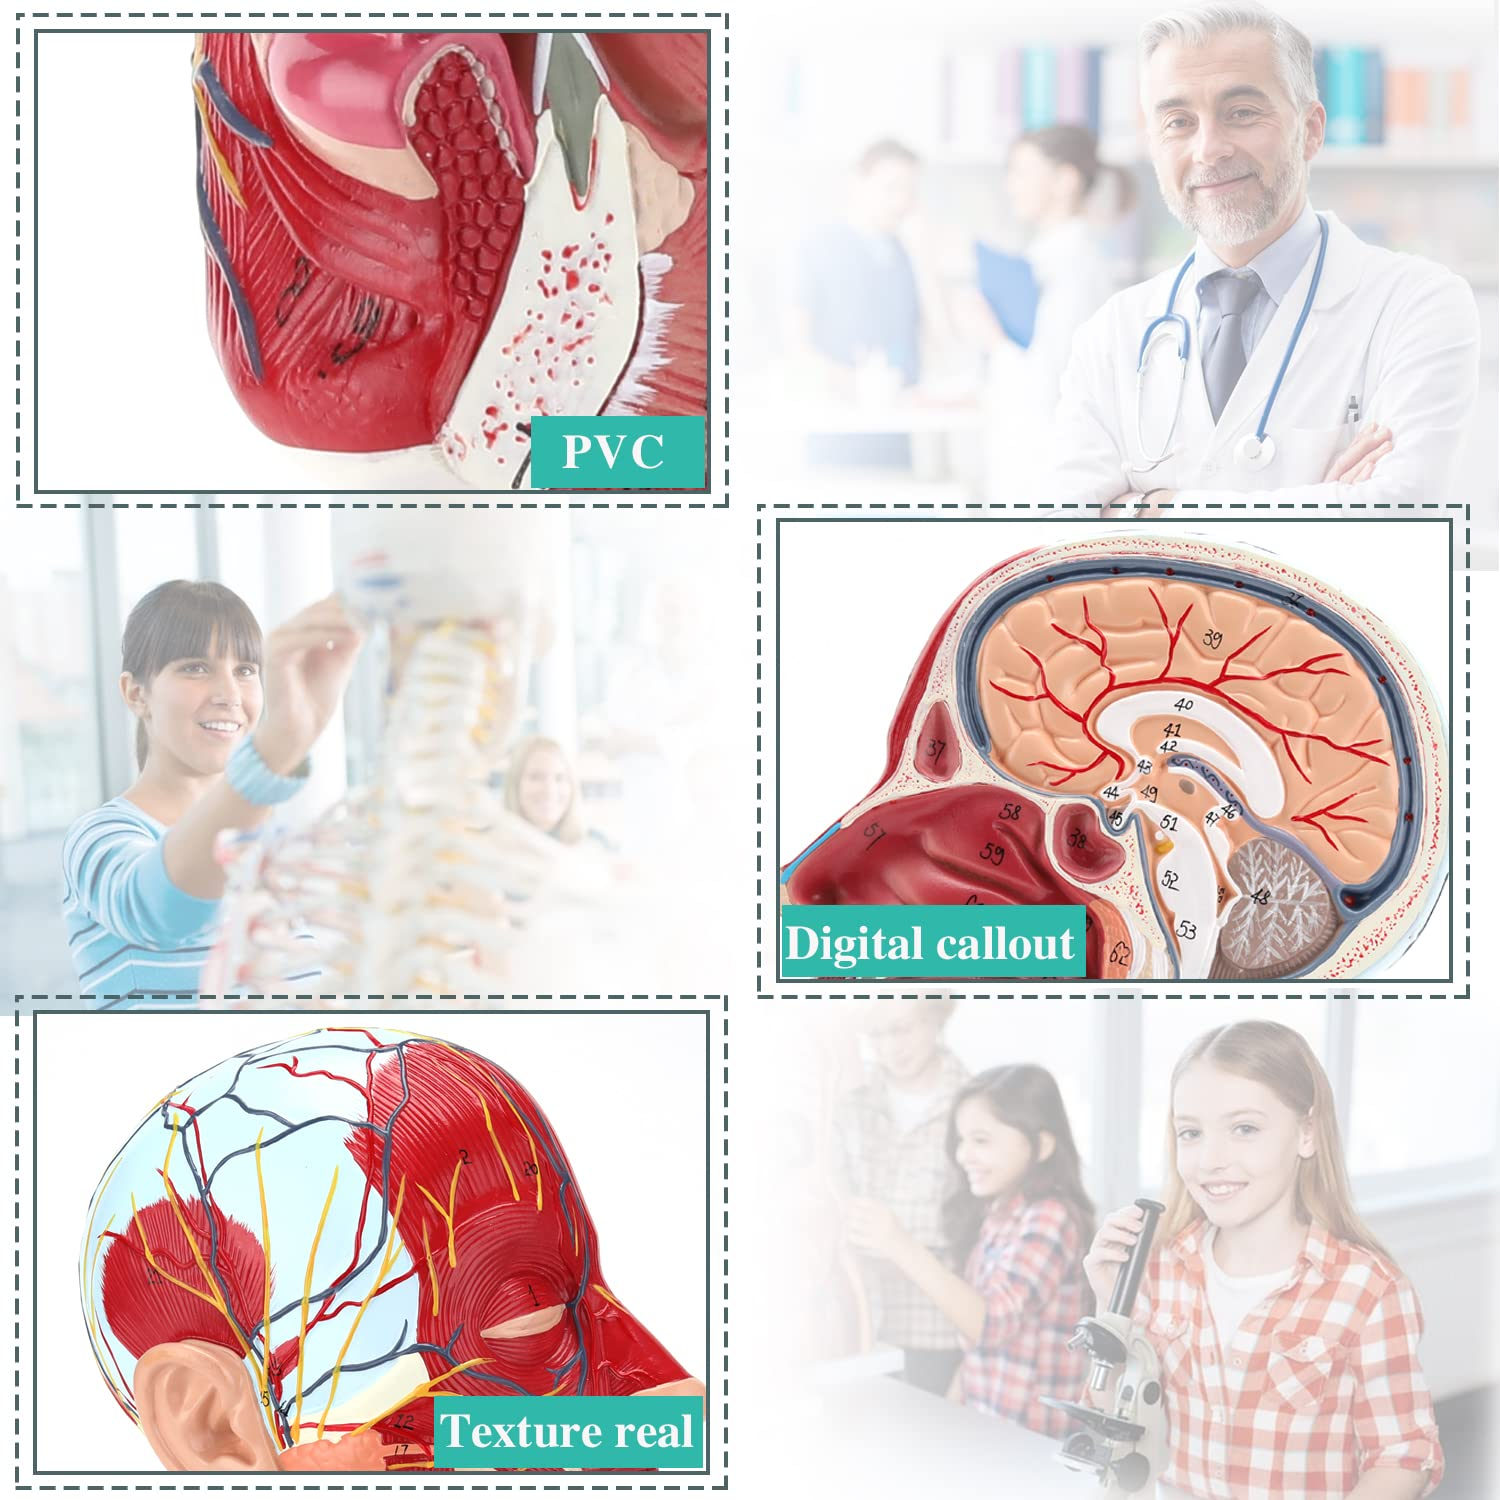

| מאַטעריאַל | פּווק |

【הויך קוואַליטעט】 מאַרך אַנאַטאָמי מאָדעל, געמאכט פון ניט-טאַקסיק ינווייראַנמענאַלי פרייַנדלעך פּווק מאַטעריאַל, גרינג צו ריין. אַנאַטאָמי מאָדעלס זענען האַנט-פּיינטיד און פארזאמלט מיט די מאַקסימאַל ופמערקזאַמקייט צו דעטאַל.